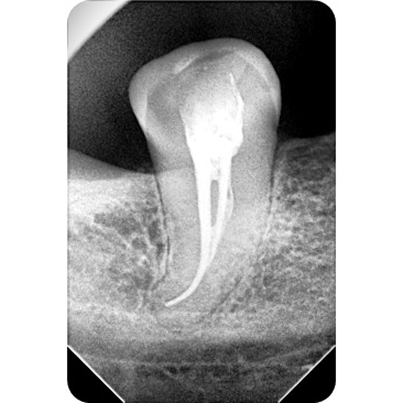

X-rays are taken to check the extent of the infection.